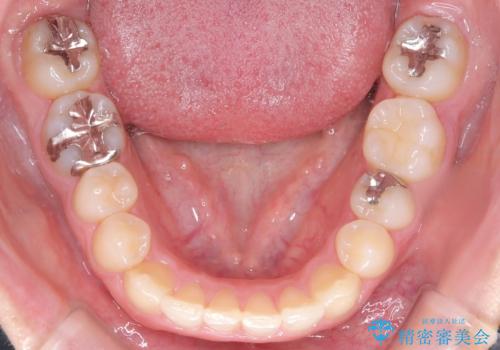

- 下の歯のがたつき(叢生)、真ん中(正中)が右にずれていることを主訴に来院されました。右上前から3番目の永久歯が埋まっている(埋伏)していることから正中は可能な限り合わせることをゴールとしてマウスピースでの矯正治療を選択しました。

今回の矯正治療では、透明なマウスピース型の装置インビザラインを使用しました。がたつきをとるため、安全性が確保できる範囲で歯と歯の間を少し削り必要なスペースを確保しました。